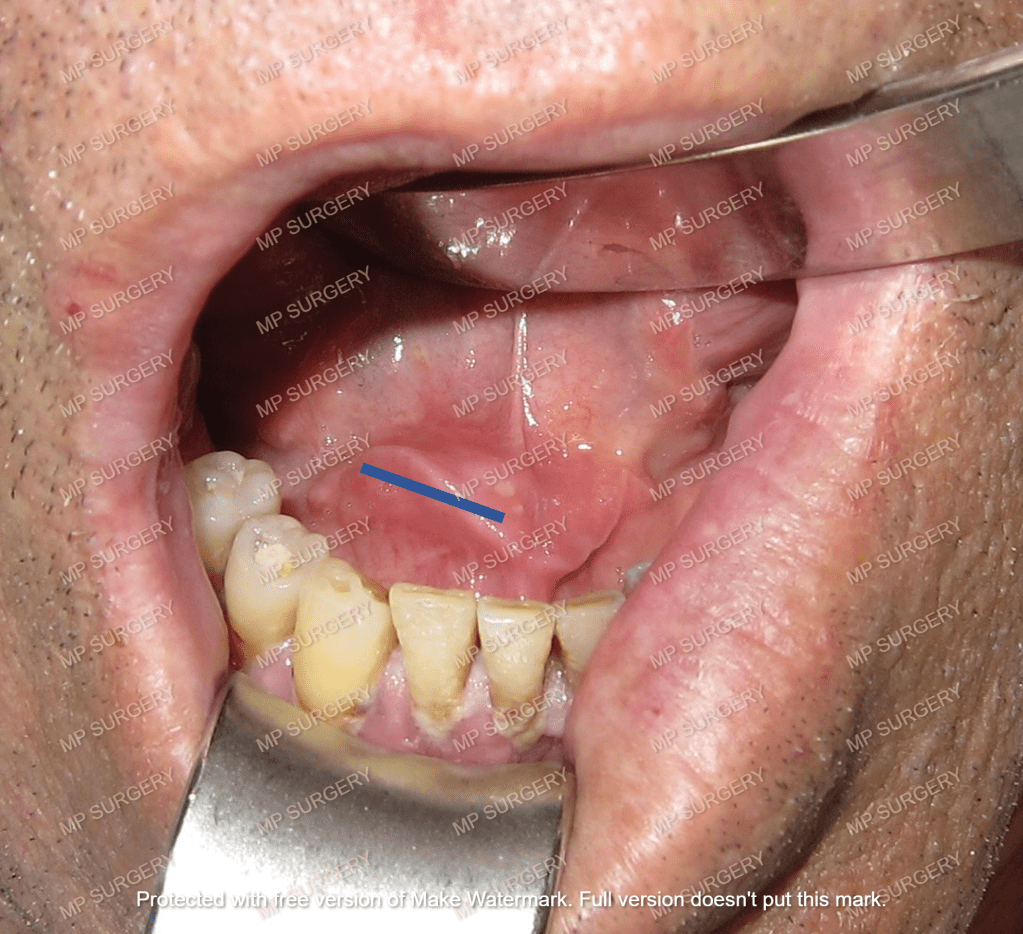

Οι σιαλόλιθοι αντιμετωπίζονται με χειρουργική αφαίρεση, όταν προκαλούν συμπτώματα.